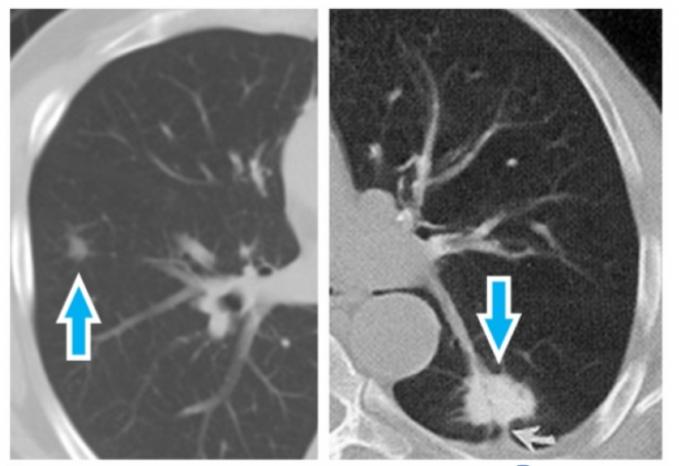

- 形狀與邊緣:邊緣是光滑、模糊,還是有分葉、毛刺狀?內部有沒有空泡或支氣管充氣徵?

- 位置:位於肺的哪一葉?週邊還是靠近中央?這影響手術處理的難易度。這些特徵共同構成我們對這個毛玻璃結節病灶風險的初步判斷。